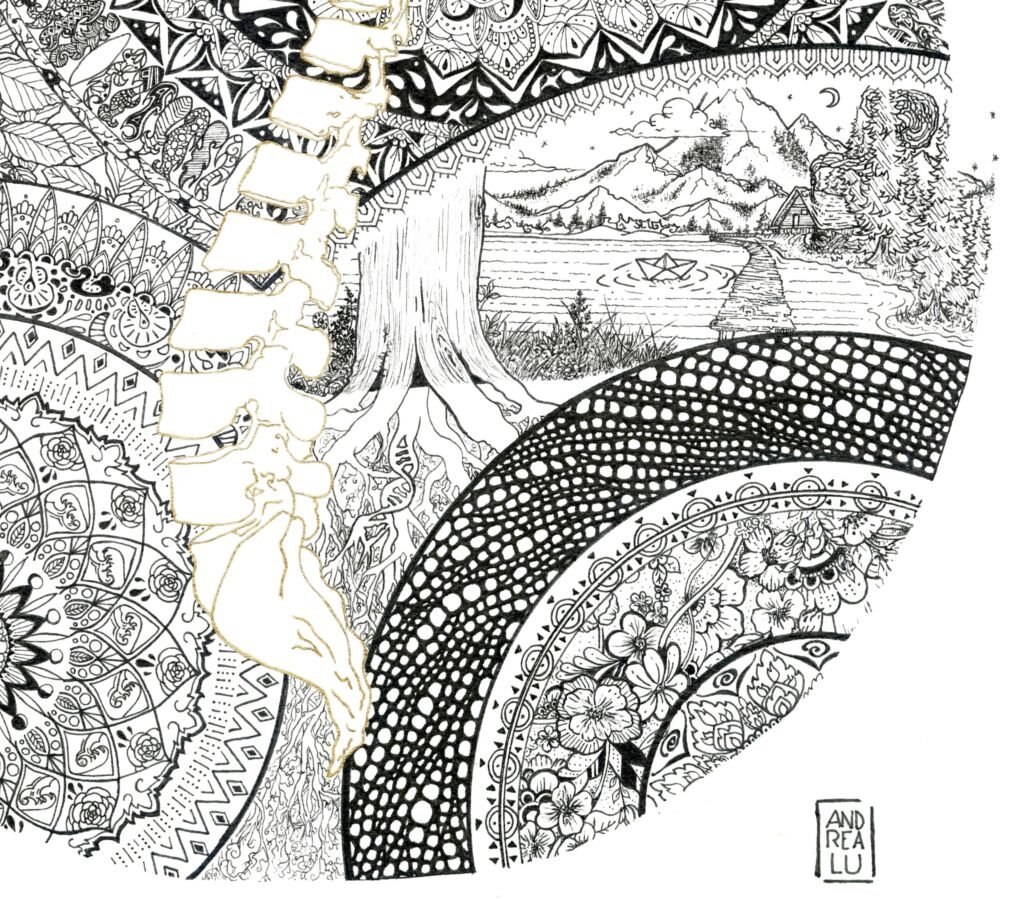

Cycle 1 – Organs – Axis

Description

Avec ce dessin, j’ai d’abord cherché à représenter ce que je ressentais lors des crises inflammatoires de la colonne vertébrale.

La colonne est un axe central, un point de passage essentiel : elle transmet l’ensemble des informations nerveuses, comme une gare où transitent les messages envoyés au cerveau.

Lorsque toute la colonne s’enflamme, la douleur ne reste pas localisée. Elle devient un feu intérieur, diffus, qui envahit progressivement l’ensemble du corps.

Ce dessin est né de cette sensation.

Il tente de traduire cette brûlure interne, cette circulation douloureuse, cette perte de frontières entre un point précis et la totalité du corps.

Puis, en avançant le long de la colonne, le dessin a évolué.

Chaque vertèbre s’est mise à résonner différemment, en fonction de ce à quoi elle est reliée.

Les cervicales, les dorsales, les lombaires ne racontent pas la même histoire, ne dialoguent pas avec les mêmes territoires du corps.

En état de pleine conscience, j’ai ressenti les vertèbres connectées à la cage thoracique, liées à la respiration — inspirer, expirer — une pulsation vitale.

D’autres, reliées à l’appareil génital, m’ont ramenée à une part plus intime, plus profondément féminine.

Organe central de notre squelette, la colonne vertébrale devient alors bien plus qu’un support.

En état méditatif, elle agit comme un point d’ancrage, un axe de présence.

Ici, la douleur ouvre paradoxalement un accès à l’instant.

Un retour au corps.

Ici et maintenant.

Détails Zoomés